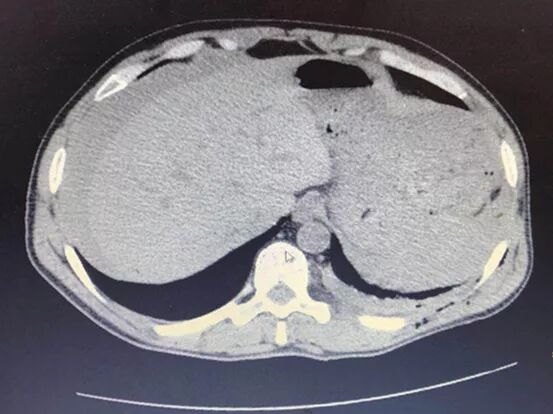

一赶到现场他们就会同当地医务人员一同参与抢救工作,据了解患者为建筑工地工人,从约6米高处坠落致颅脑、胸腹腔等多处严重骨折、外伤,患者已经出现血压降低、意识淡漠情况,但是家属考虑县医院的救治条件不足准备将伤者转往成都救治,不说到成都需要10多个小时,就是到最近的甘孜州人民医院最快也要6个多小时,目前患者已经出现严重休克根本无法耐受长途转运,当地医生告诉家属孙医生和陈医生就是成都来的“门巴(医生)”,并将伤情的严重程度一并告知家属,最终家属同意在县医院手术抢救。此时,时间就是生命,秉持“仁爱济民,勤慎服务”精神的我院医务人员拉开了同死神赛跑的脚步。在完成相关手续后我院医务人员立即将患者送入手术室,而此时患者麻醉后血压仅为43/25mmHg,心率158次每分,血氧饱和度更是无法测量,立即开腹探查腹腔积血>2000ml,并有大量凝血块,结肠脾区挫伤,脾脏碎裂严重,出血较为迅猛,快速切除脾脏止血,同时发现左侧膈肌被断裂肋骨撕破,吸出左侧胸腔积血约300ml,并行膈肌修补。因当地没有血库,医院也没有血液回输条件,但患者急需用血,在县医院领导的帮助下,当地武警官兵踊跃献血,经过五个多小时的抢救手术,在大家的共同努力下,患者生命体征稳定。